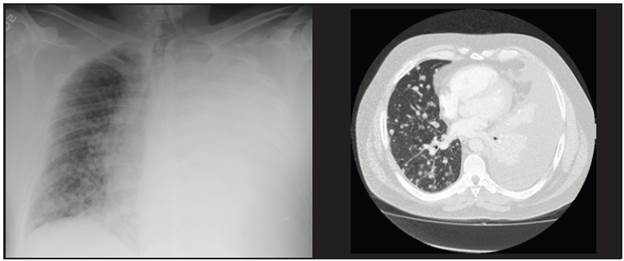

This was a 57-year-old patient with papillary thyroid carcinoma (initial stage IVB, T3bmN1bM1), treated initially with a total thyroidectomy along with central lymph node compartment and left modified radical emptying. The pathology showed 10 lymph nodes from the central emptying and 13 lymph nodes from the left modified radical emptying affected by the tumor, with no extracapsular extension, and a postoperative thyroglobulin of 8,557 ng/mL. A high-resolution chest CT was therefore ordered, which corroborated metastatic lung involvement in both lung fields. He received adjuvant therapy with 200 mCi of radioactive iodine (I-131), with no uptake on tracing, and it was therefore diagnosed as non-iodine-avid disease. Five months later he developed progressive dyspnea with radiological confirmation of a massive left pleural effusion which required thoracentesis on multiple occasions.

A cytochemical study of the pleural fluid was compatible with lymphocytic exudate, and the cytological study suggested papillary thyroid carcinoma involvement. The thyroglobulin level in the pleural fluid was markedly elevated at 7,046 ng/mL, confirming pleural involvement due to papillary thyroid carcinoma. At this point he had a serum thyroglobulin of 4,009 ng/mL, negative antithyroglobulin antibodies at 0.83 IU/mL (reference value < 4.11 IU/mL) and a TSH of 0.05 uIU/mL. A new tomography showed pulmonary disease progression according to the Response Evaluation Criteria in Solid Tumors (RECIST). He was considered to be a candidate for treatment with tyrosine kinase inhibitors. However, the patient developed severe SARS-CoV-2 pneumonia with acute respiratory distress syndrome (ARDS), requiring prolonged mechanical ventilation, and is currently at ECOG 3 with severe physical deconditioning syndrome, which has delayed the initiation of sorafenib.

This was a 63-year-old patient with the classical variant and follicular infiltrative variant of papillary thyroid carcinoma, initially stage IVB, T2mN1bM, who underwent total thyroidectomy with central compartment and left modified radical emptying. She had one positive lymph node in the central emptying and three affected lymph nodes in the left modified radical emptying, none with extracapsular extension. The postoperative thyroglobulin was 130.6 ng/mL and antithyroglobulin antibodies were negative. Therefore, a high-resolution chest tomography was performed showing micronodular involvement in both lung fields. Adjuvant therapy with I-131 was administered, with a total of 300 mCi received and post-therapy tracing showing no pulmonary uptake. It was decided to administer TSH suppression treatment with levothyroxine, and the patient showed clinical stability for the following three years. In the fourth year, she developed dyspnea and right-sided pleuritic chest pain with a chest x-ray showing right pleural effusion. She underwent thoracentesis, with a cytochemical study of the pleural fluid compatible with lymphocytic exudate and an immunohistochemical study of the pleural fluid positive for PAX8 and calretinin and negative for WT-1, D2-40, TTF-1 and thyroglobulin. These findings are highly suggestive of metastasis from a papillary thyroid carcinoma. The patient had a recurrent pleural effusion, and therefore it was decided to perform talc pleurodesis. To date, she has had no further episodes of pleural effusion. The proper time for beginning tyrosine kinase inhibitors will be determined with the patient based on the results of new tomographic studies.